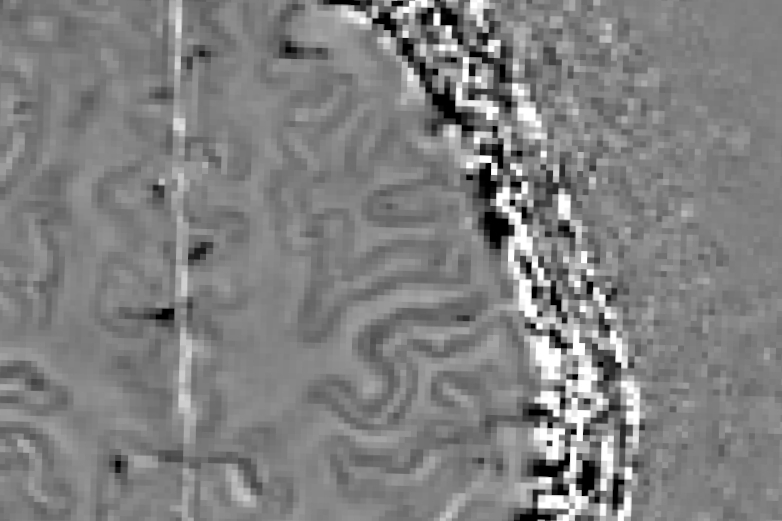

BIaaS (Brain-Iron-as-a-Service) permet de visualiser les accumulations de fer dans les lésions et de catégoriser celles-ci en termes d’activité et d’évolution. Cette solution pourrait aussi participer à la caractérisation du signe de la veine centrale (SVC).

La manifestation du fer, à travers le signe de la veine centrale et le halo paramagnétique, fait désormais partie des critères internationaux de McDonald pour diagnostiquer et suivre la SEP (version révisée en septembre 2025).